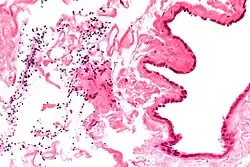

The primary care physician may diagnose and manage benign causes of scrotal masses such as hydrocele, varicocele and spermatocele. However, if a "must not miss" diagnosis related to testicular masses such as testicular torsion, epididymitis, acute orchitis, strangulated hernia and testicular cancer is suspected, the family physician must refer to a urologist.[19] Finding a painless, cystic mass at the head of the epididymis that is clearly separate from the testicle can indicate a spermatocele. Shining a light through the mass, a process known as transillumination, can also help differentiate between a fluid-filled cyst and a tumor, which would not allow as much light to pass.[20] If uncertainty exists, ultrasonography of the scrotum can confirm the presence of a spermatocele.[7] The location and history of any scrotal masses are crucial in determining whether or not the mass is benign or malignant.[21] Lab tests such as a complete blood count (CBC test) or urine test can also be conducted to check for any possible infection or signs of inflammation.[22]

Spermatoceles come in varying sizes and shapes. Some spermatoceles are very small and can only be detected through an ultrasound. More commonly seen are spermatoceles that are a pea-sized lump. They tend to form above or behind a testicle and have a shape and size that looks like a pea. Larger growths have been reported to look similar to a third testicle and can be very discomforting.[22] For those who are affected with large spermatoceles, some have reported feeling pain, heaviness, and fullness in the affected testicle.[20]